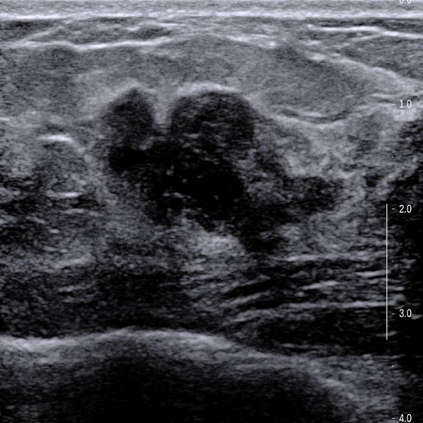

Ultrasonography is an important routine examination for breast cancer diagnosis, due to its non-invasive, radiation-free and low-cost properties. However, it is still not the first-line screening test for breast cancer due to its inherent limitations. It would be a tremendous success if we can precisely diagnose breast cancer by breast ultrasound images (BUS). Many learning-based computer-aided diagnostic methods have been proposed to achieve breast cancer diagnosis/lesion classification. However, most of them require a pre-define ROI and then classify the lesion inside the ROI. Conventional classification backbones, such as VGG16 and ResNet50, can achieve promising classification results with no ROI requirement. But these models lack interpretability, thus restricting their use in clinical practice. In this study, we propose a novel ROI-free model for breast cancer diagnosis in ultrasound images with interpretable feature representations. We leverage the anatomical prior knowledge that malignant and benign tumors have different spatial relationships between different tissue layers, and propose a HoVer-Transformer to formulate this prior knowledge. The proposed HoVer-Trans block extracts the inter- and intra-layer spatial information horizontally and vertically. We conduct and release an open dataset GDPH&GYFYY for breast cancer diagnosis in BUS. The proposed model is evaluated in three datasets by comparing with four CNN-based models and two vision transformer models via a five-fold cross validation. It achieves state-of-the-art classification performance with the best model interpretability.

翻译:超声波分析是乳腺癌诊断的一个重要常规检查,原因是其非侵入性、无辐射和低成本的特性。然而,由于其内在局限性,它仍不是乳腺癌的第一线筛选测试。如果我们能够精确地通过乳房超声图像诊断乳腺癌(BUS),它将是一个巨大的成功。我们提出了许多基于学习的计算机辅助诊断方法,以实现乳腺癌诊断/感官分类。然而,其中多数方法需要事先确定性能模型,然后对ROI内部的跨值进行分类。常规分类支柱,如VGG16和ResNet50等,可以在没有ROI要求的情况下实现有希望的分类结果。但是这些模型缺乏可解释性,从而限制了其在临床实践中的使用。在本研究中,我们提出了一个新的无乳腺癌诊断模型,在超声波图像中进行解释性特征描述。我们利用了先前的解剖学学学知识,即恶性肿瘤和良性肿瘤模型在不同组织层之间有着不同的空间关系,并提议采用状态解析法来编制这一先前的知识。拟议中的HOVer-Trans-Trading-Tradef-trainal Ex-deal-dealal-deal-deal-deal-degraphal-deal-deal-deal-deal-deal-deal disal disal-dal-dal-dal-dal-dal-deal-deal-dal-deal-deal-deal-dal-dal-dal-dal-dal-dal-dal-dal-dal-dal-dal-dal-dal-dal-I-dal-Iversal-dal-Ial-d-d-I-d-d-I-I-I-I-I-I-I-I-I-I-I-I-I-I-I-I-I-I-I-I-I-I-I-I-I-Ial-I-Ial-Ial-I-I-I-I-I-I-I-I-I-I-I-I-I-I-I-I-I-I-I-I-I-I-I-I-I-I-I-I-I-I-I-I-